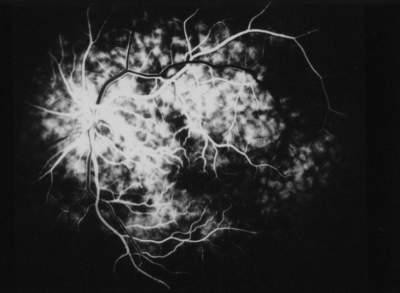

Die Allgemeinanamnese und die Augenanamnese der Patientin sind unauffällig. Die zentrale Sehschärfe beträgt mit Korrektur (-3,5 D sph. bds.) beidseits 1,0. Die Tensio liegt im Normbereich (12 / 13 mmHg). Der Spaltlampenbefund der vorderen Augenabschnitt ist regelrecht. Ophthalmoskopisch lassen beide Fundi mit vitaler, randscharfer Papille, unauffälliger Makula und normalen Gefäßen einen regelrechten Befund erkennen. Die durchgeführte Computer-Perimetrie (Octopus) ergibt eine unspezifische Dämpfung im peripheren Gesichtsfeld rechts. Subjektiv war die Patientin zum Zeitpunkt der Untersuchung völlig beschwerdefrei. Am gleichen Tage wurde bei der Patientin eine FLADOP durchgeführt. Im Verlauf der angiographischen Aufnahme erkennt man, wie sich die temporale Fundushälfte unauffällig füllt. Die lobuläre Füllungsphase nimmt hier ihren Ausgang von vier verschiedenen temporalen Aderhautsegmenten (Abb. 49 ). Bei einem intraokularen Druck von 55 mmHg ist die lobuläre Füllungsphase der temporalen Fundushälfte abgeschlossen, während nasal der Papille die Füllung der großen Aderhautgefäße noch nicht begonnen hat. Auffallend ist außerdem, daß an der Grenzlinie zwischen den beiden Gebieten vollständig gefüllte Aderhautlobuli und nicht fluoreszente Aderhautlobuli unmittelbar nebeneinander liegen ( Abb. 48 ). Eine solche Demarkierungslinie finden wir nicht bei Augengesunden. Erst unter einem intraokularen Druck von 30 mmHg füllt sich bei der Patientin auch die nasale Choriokapillaris. Das Aderhautprofil (Abb. 49 ) zeigt die entsprechende Füllungsverzögerung mit einem steilen Abfall des Profils nach nasal. Aufgrund der größflächigen Verzögerung läßt sich schließen, daß hier eine Perfusionsstörung eines nasalen Hauptastes der hinteren Ziliargefäße vorliegt. Die Perfusionsdruckspanne der Aderhaut (AH-PDS) ist mit 51 mmHg gegenüber dem augengesunden Kontrollkollektiv hochsignifikant verzögert (Irrtumswahrscheinlichkeit = 1%) und somit als pathologisch anzusehen. Da bei der Patientin keine allgemein-internistischen Erkrankungen vorliegen, die als Ursache dieser Durchblutungsstörung gewertet werden können, muß hier eine primäre Aderhautperfusionsstörung angenommen werden. |

Abb. 48 S.A.., weiblich, 18 Jahre primäre Aderhaut-Durchblutungsstörung der medialen hinteren Hauptziliararterie (IOD = 60 mmHg) |